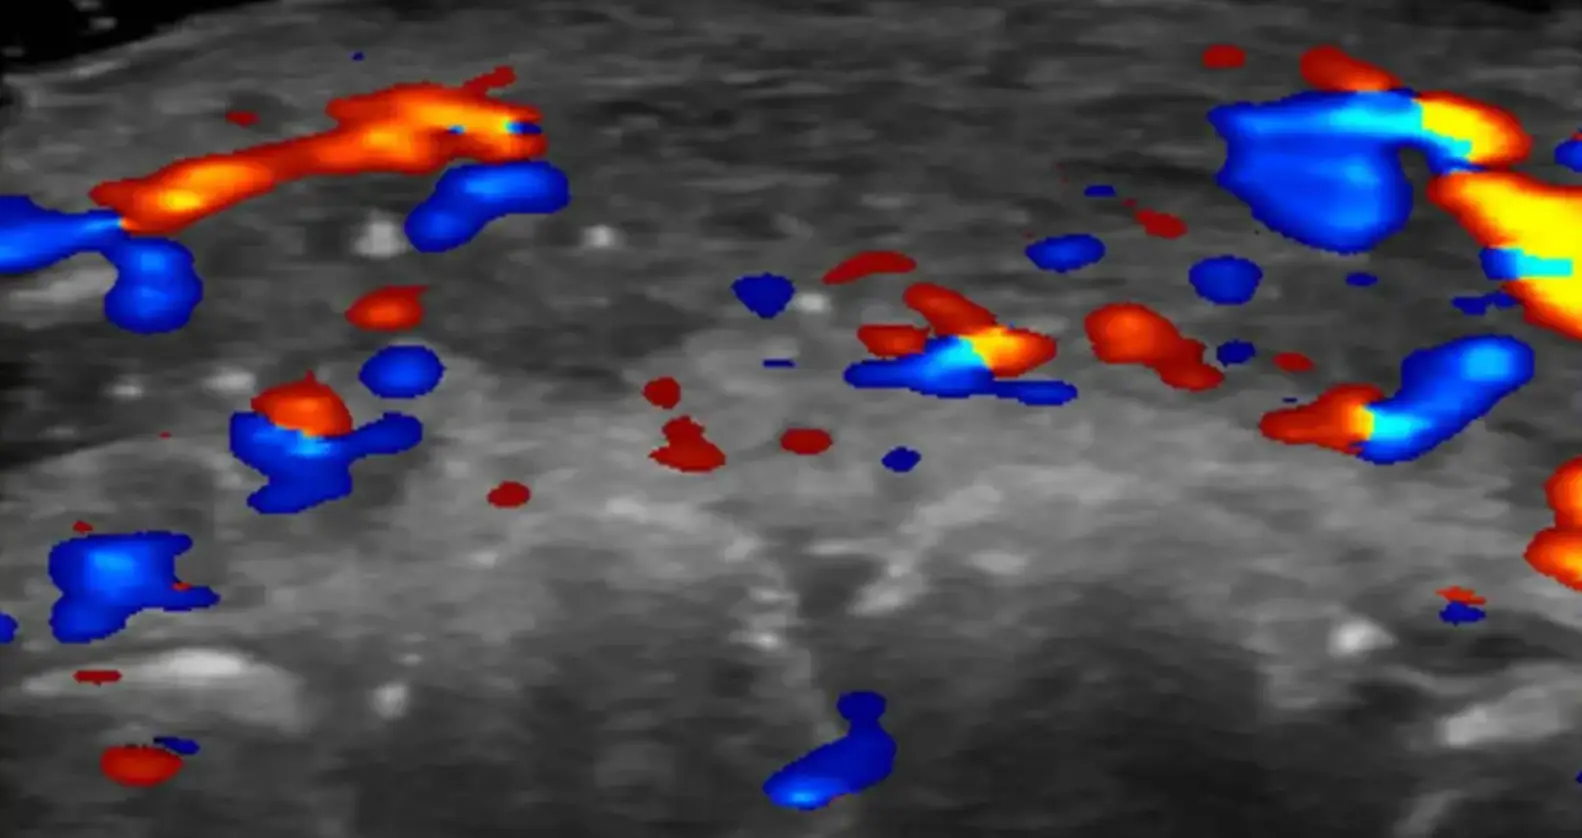

An ultrasound was performed on 100 individuals who've received considerable dermal fillers in recent years, with lead researcher Dr Rosa Sigrist telling the BBC that her team at the University of São Paulo in Brazil observed cases of 'vascular occlusion'.

In just less than 50 percent of cases, these scans showed absent blood flow to a number of small vessels connected to both superficial arteries and those found deeper inside the face.

A third of patients studied also showed an absence of blood flow in several major blood vessels.

As such, Dr Sigrist is now emphasising the importance of aestheticians performing scans on their patients whilst administering fillers into their faces.

"If injectors are not guided by ultrasound, they treat based on where the clinical findings are and inject blindly," she explained. "But if we can see the ultrasound finding, we can target the exact place where the occlusion occurs."

Dr Sigrist also recommended clinicians performing guided injections with ultrasound scans that use less hyaluronidase, as opposed to over-flooding the area with this drug.